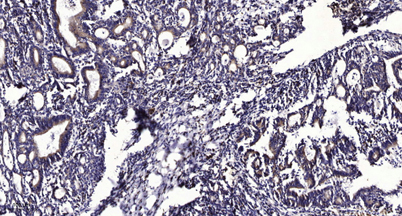

Applications’╝ÜWB;ELISA;IHC

Õģ│µ│©ÕŠ«õ┐ĪÕģ¼õ╝ŚÕÅĘ

ÕŠ«õ┐Īµē½õĖƵē½Ķ┐×Õ┐ÖÕÆ©Ķ»ó

ÕŠ«õ┐Īµē½õĖƵē½Ķ┐×Õ┐ÖÕÆ©Ķ»ó